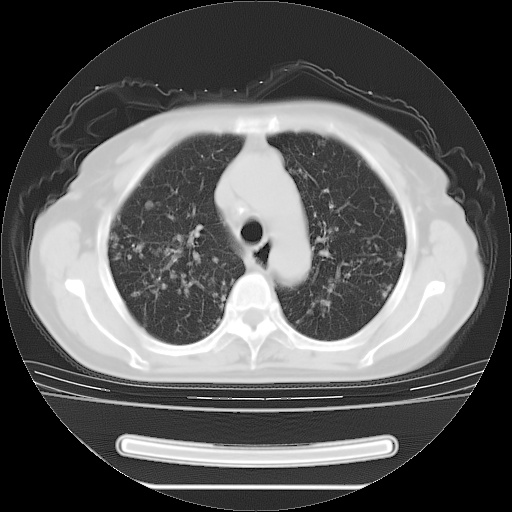

ct示两肺粟粒状病灶,以两肺上叶尖后段及下叶背段分布为主;首先考虑结核。请战友们分析。

考虑 1 弥漫性泛细支气管炎, 2 结核不除外/.  有小叶中心结节 和 树芽征!!

两肺内病灶呈小结节状和树芽状,纵膈的肿大的淋巴结密度不均匀,并见有钙化,考虑为两肺结核可能更大些。

两肺内病灶呈小结节状和树芽状,纵膈的肿大的淋巴结密度不均匀,并见有钙化,多形态病灶,考虑为两肺结核,肝内考虑小囊肿。

病灶以结节为主,大部分边界清楚,分布不均,病灶形态较单一,偶见空泡征,纵膈淋巴结肿大钙化,无结核中毒症状考虑 感染性病变【真菌类可能性大】,细支气管肺泡癌。其他待排

两肺内病灶呈小结节状和树芽状,纵膈的肿大的淋巴结密度不均匀,并见有钙化,结合(曾抗炎治疗无效果,最近抗结核治疗约半月余,症状缓解。)

考虑为两肺结核可能更大些。

纵隔见肿大淋巴结并钙化,首先考虑结核,但感觉小结节像“挂果”征,分布位于支气管边缘,所以不排外肺泡癌,建议抗唠后复查吧?不然是癌的话,也不好治吧?化疗?